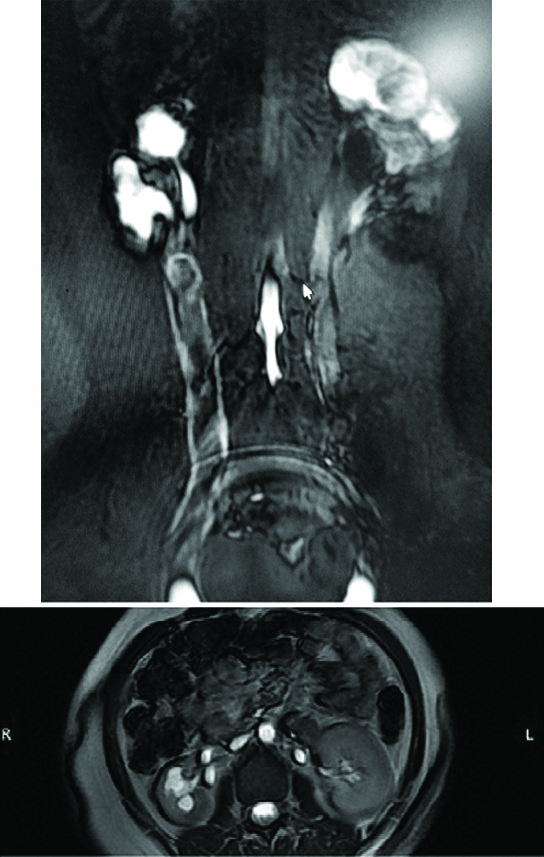

A systemic examination was done which was unremarkable. Urinalysis and a complete blood count were essentially normal. An ultrasound showed bilateral duplex moiety with bilateral hydronephrosis and right ureter was dilated. Computed Tomography (CT) scan showed triple calyceal system with hydronephrosis on right side. The three ureters joined at upper part at L3 level, forming a dilated common ureter which drains below bladder neck along with complete duplication on left side with gross hydronephrosis of upper moiety. The upper moiety ureter was ectopic draining below bladder neck and lower moiety ureter was normally opening at trigone. Magnetic Resonance Urography (MRU) was suggestive of trifurcate right renal pelvis with dilated right ureter opening ectopically into vaginal vault. Duplex moiety of left kidney with hydronephrosis of upper moiety with ectopic opening of upper ureter into vaginal vault [Table/Fig-1].

Magnetic resonence urogram-showing right side triple ureter.